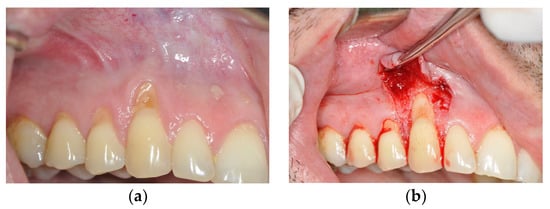

The examination within this comparative prospective study was performed on 20 patients, aged 20–45 years, who were non-smokers, who met the following criteria: the presence of gingival recession (class I and II according to Miller’s classification or class RT1 according to the EFP classification published in 2019) on canines with a visible and preserved cement–enamel junction on the buccal side of two teeth that were located in the same jaw contralaterally. The surfaces in the recession area had to be caries-free and intact on the buccal surface. All patients were treated at the Dental Clinic of the Military Medical Academy in Belgrade. On one side of the jaw, recessions were treated using a de-epithelialized gingival graft in combination with a coronally advanced flap of partial thickness (DGG group) (Figure 1). On the other side of the jaw, gingival recessions were treated with the application of growth factors—plasma-rich fibrin in combination with a coronally advanced flap of full thickness (PRF group) (Figure 2).

Figure 2.

Gingival recession on tooth #23 treated with platelet rich fibrin (PRF) and coronally advanced flap (CAF). (a) Gingival recession before the treatment; (b) incision made at the site of the recession; (c) PRF placed at the site of the recession; (d) one month post-operation.